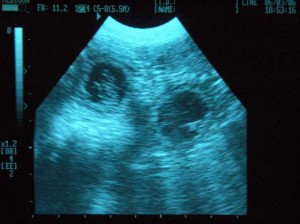

Toto je jej posledný ultrazvuk.žeby čakala dvojčky?